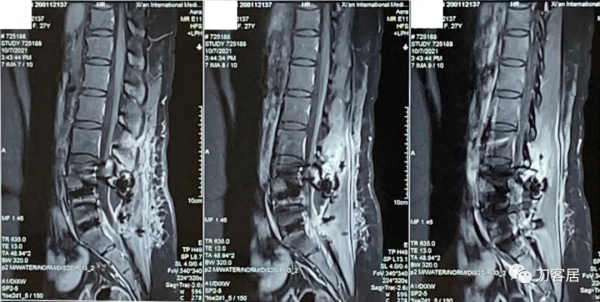

圖2. 20210817術前腰椎MRI矢狀面T2相,提示腰4-5,腰5骶1椎間盤突出,腰4-5椎間盤應該脫落進入椎管內,腰5椎體後緣了。

圖3. 20210817術前腰椎MRI矢狀面T2相,提示腰3-4-5-骶1椎間盤突出,腰3-4很輕,無需處理,腰4-5突出較大。

圖4. 20210817術前腰椎MRI矢狀面T1相,提示腰3-骶1椎間盤突出,腰4-5較大。